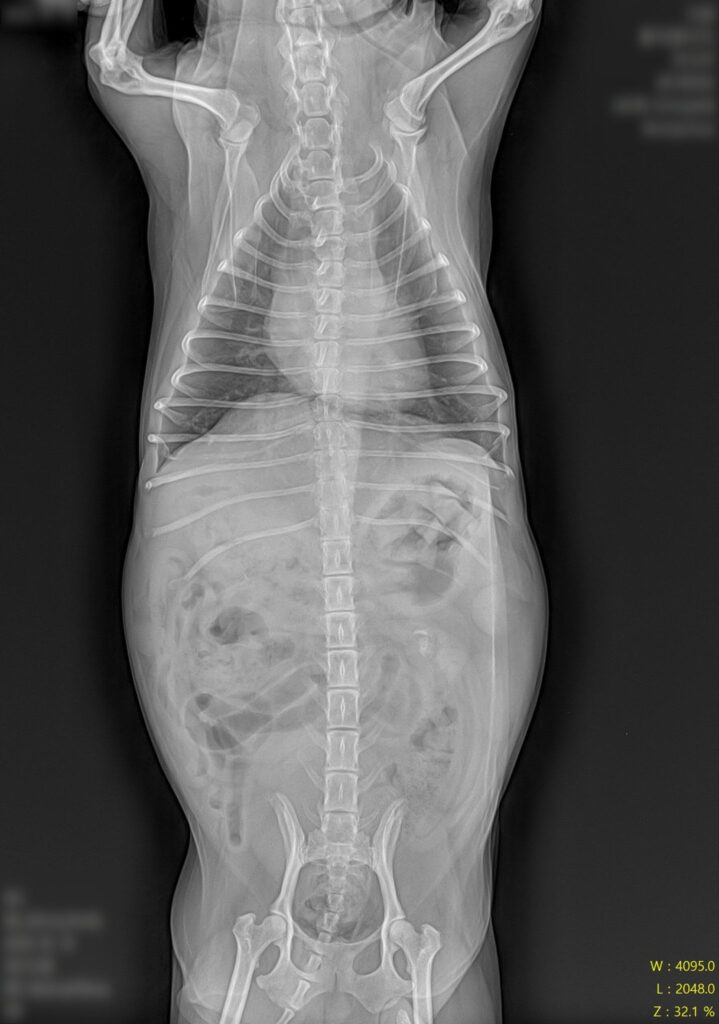

마취 전 혈액검사와 방사선 검사를 통해 마취 가능 여부를 먼저 확인했습니다. 12세 고령 환자인 만큼 수술 전 전신 상태를 꼼꼼히 평가하는 과정이 특히 중요했어요.